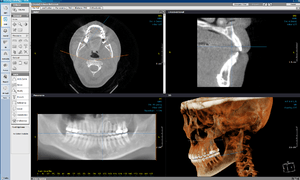

OnDemand3D

Having had popular predecessors such as V-Works(2000) and CB-Works (2004), OnDemand3D was introduced in 2006 as a 'complete dental imaging solution'.[4] It is a 3D image processing software written in C/C++ on MFC available in English, French, Spanish, German, Russian, Japanese, Polish and Portuguese.[5] It is a module-based software, where the user can customize according to their diagnostic or research needs.[6]

OnDemand3D is sold in two main packages; one being OnDemand3D App and the other being OnDemand3D Dental.[7] The difference is in the modules included, briefly summarized in the table below.